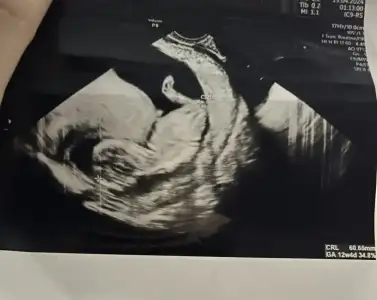

• Screenshot_2024-04-26-22-05-57-31_99c04817c0de5652397fc8b56c3b3817.webp

Screenshot_2024-04-26-22-05-57-31_99c04817c0de5652397fc8b56c3b3817.webp

11,4 KB · Görüntüleme: 39